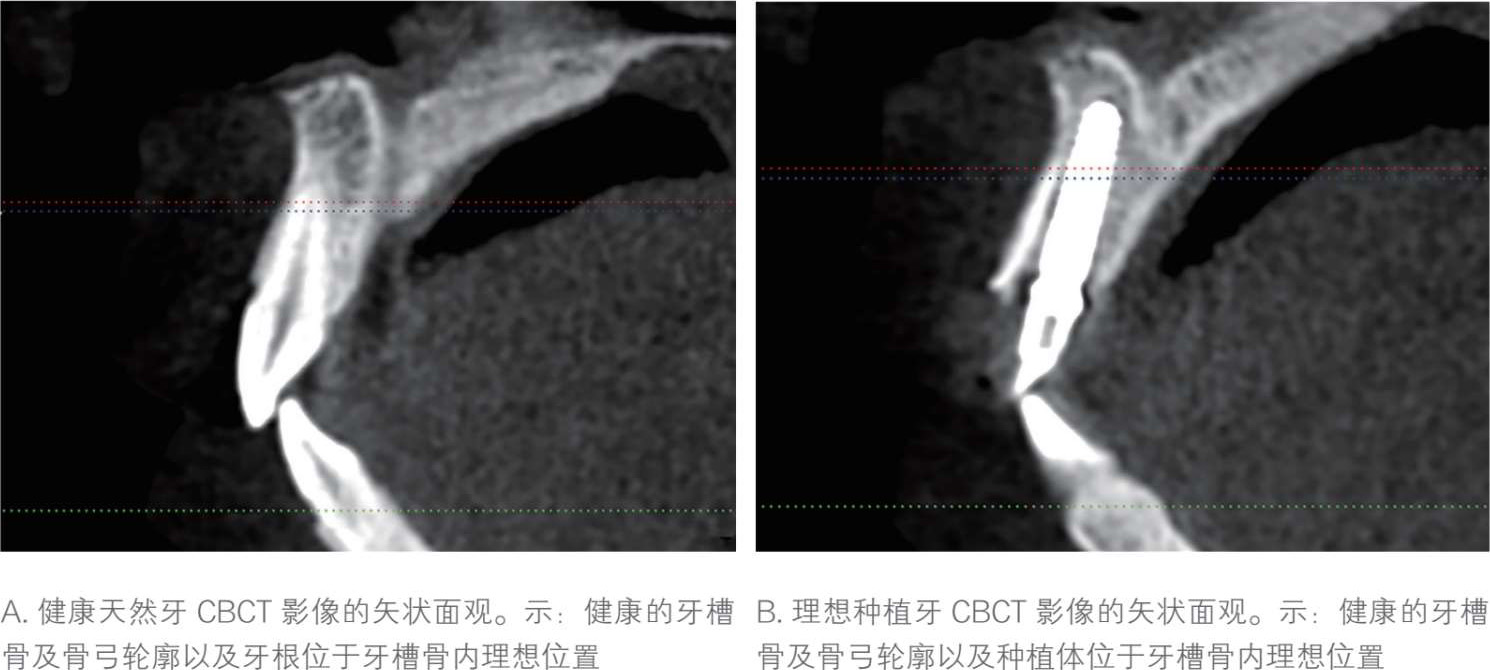

“咀嚼、美观、辅助发音”是健康天然牙的主要生理功能。为了长期维持上述功能,除了需要有健康牙槽骨、牙周膜、牙龈等牙周解剖条件,还需要天然牙位于牙槽骨中的合理位置(图 1-1-1 A),上下牙列的牙齿排列为整齐连续的牙弓弧线,并且后牙形成完美的尖窝对应关系,前牙保持正常的覆

覆盖。当上述任何一个要素出现问题或不理想时,天然牙的生理功能就无法有效实现或长期维持。

与天然牙相似,种植牙功能的实现与维持也是建立在一定的解剖生理条件下的。布伦马克(Brånemark)教授提出的“骨结合”理论是当今种植技术最为根本的基础理论,即在光镜下,种植体表面和活骨直接接触,没有纤维等其他组织包绕,并且二者间呈现不同比例接触面积。足量、稳定的种植体骨结合是种植体在患者口腔内长期健康留存的基本条件。除了健康的骨结合、软组织生物学封闭等种植体周解剖条件,种植牙理想功能的实现还需以下要素,包括每颗种植体位于牙槽骨中合理的位置(图 1-1-1 B),多颗种植体之间合理分配空间并保证一定的平行度,所支持的上部修复体在后牙区域形成完美的尖窝对应关系,在前牙区域维持正常的覆

覆盖。当种植修复的结果满足以上全部要素条件时,即意味着医生实现了“以修复为导向”的种植治疗效果,使最终修复体接近健康天然牙状态(图1-1-2)。

图 1-1-1 健康天然牙和理想种植牙锥形线束CT(cone beam computed tomography,CBCT)影像